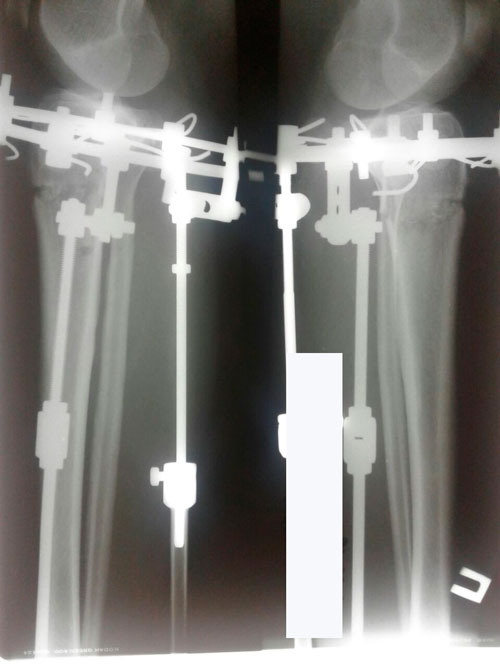

Дата операции 21.03.2018г.

Дата снятия аппаратов 06.07.2018г.

Срок лечения 105 дней.